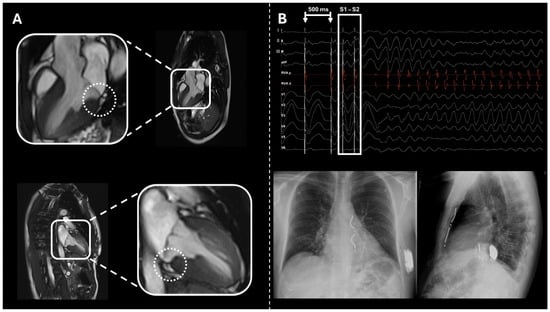

2.1. Case 1

2.2. Case 2

2.3. Case 3

2.4. Case 4

2.5. Case 5